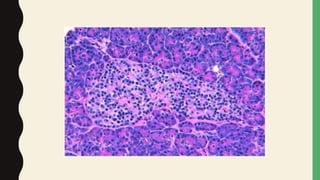

PATHOPHYSIOLOGY

• An inflammatory process caused by pancreatic autodigestion

– Cell damage

– Activate trypsinogen & inflammatory mediators

– Potentiate feedback loop

• Chronic pancreatitis-

– progressive inflammatory changes

– Leads to structural damage

– Impaired endocrine & exocrine function

– significant fibrosis- enzymes are not elevated